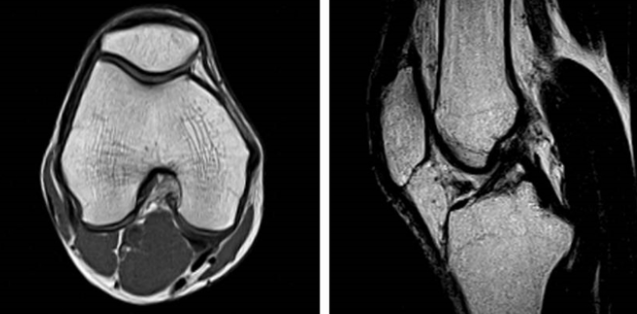

MRI 건강보험 적용